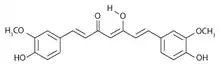

| Curcumin-keto | .svg.png.webp) Curcumin_structure_(Keto) |

| Curcumin-enol |  Curcumin-enol |